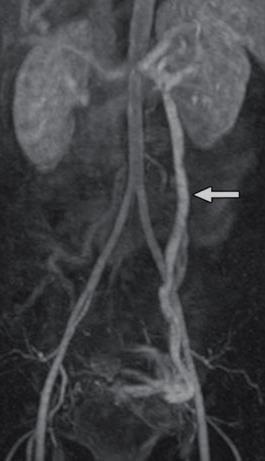

左肾静脉回流异常(前胡桃夹子综合症-anterior Nutcracker Syndrome)

后胡桃夹子综合症 posterior Nutcracker Syndrome

Acquisition during a venous phase (80’’) :